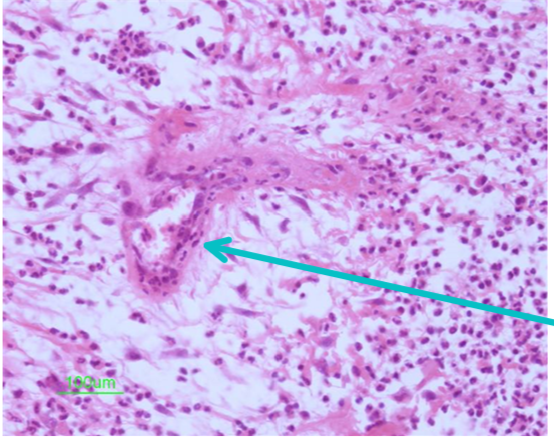

Identify this structure:

capillary buds located within granulation tissue